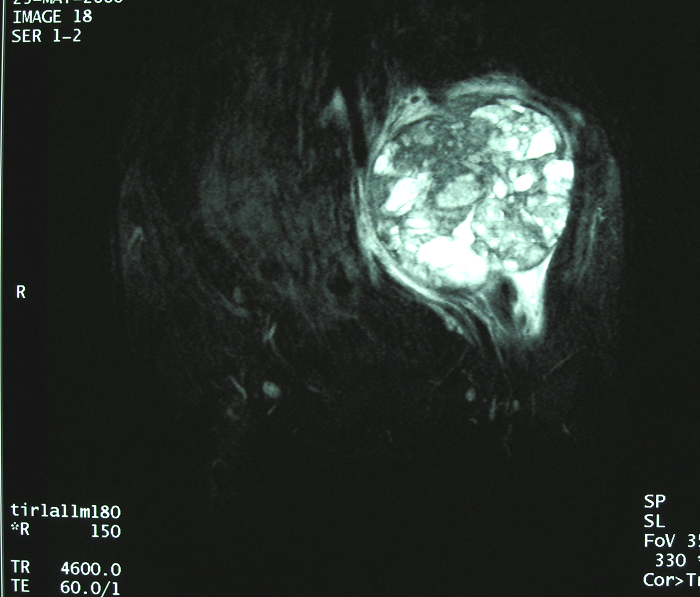

6、病例6:女 18岁 左半骨盆骨肉瘤,全身及肿瘤局部选择性动脉灌注大剂量化疗后行肿瘤切除人工半骨盆假体置换术

图 37 术前MRI